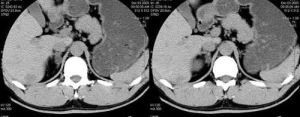

3、少見內分泌大量固酮的腎上腺皮質癌,往往還分泌糖皮質類固醇,雄激素腫瘤體積大,直徑多在3cm以上,切面常顯示出血,壞死,腫瘤的惡性性質在細胞學上常難以確定,轉移灶的存在得以確診。